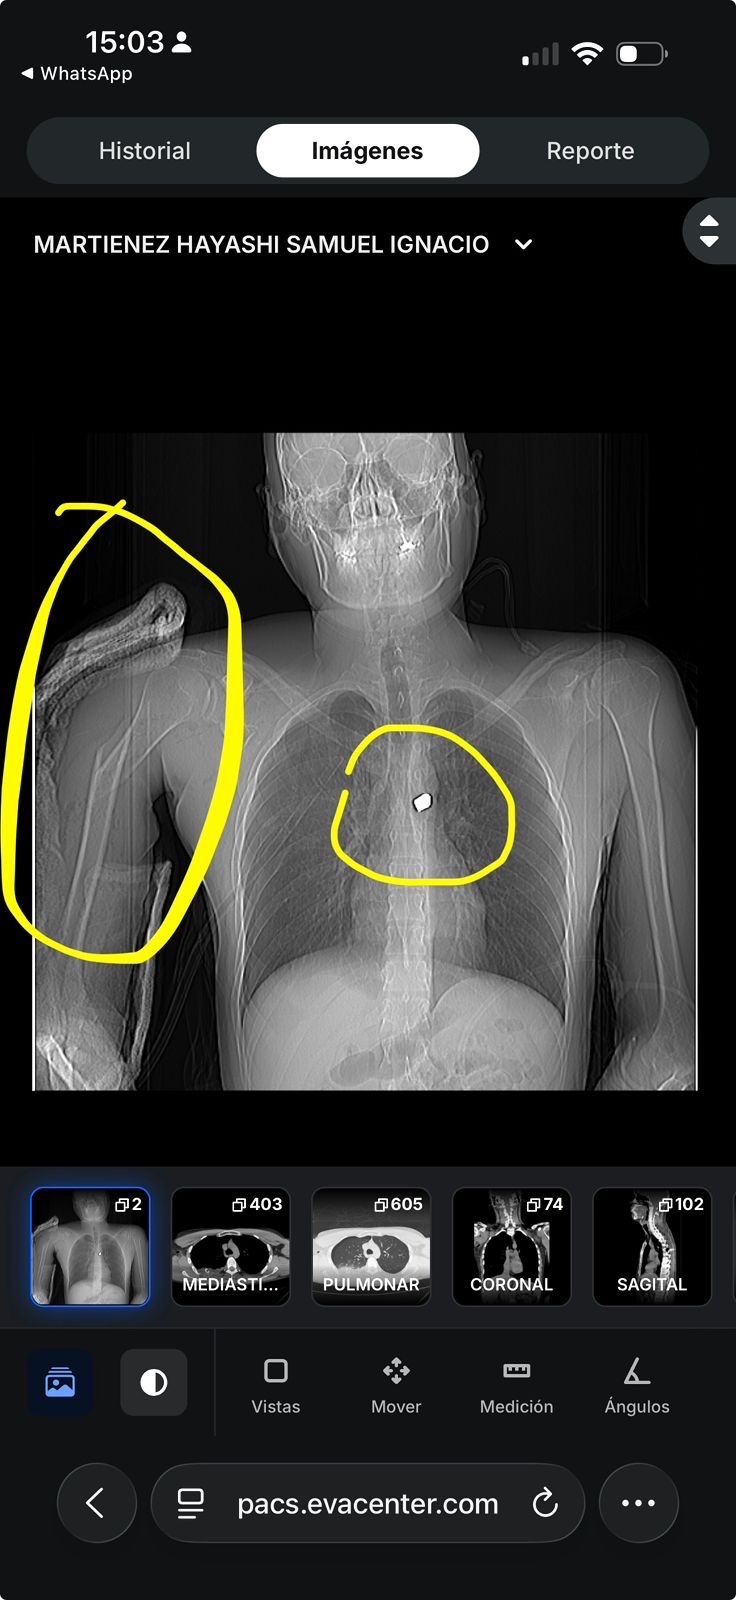

Fue víctima de un asalto a mano armada, el cual, el asaltante le disparó a quemaropa. Impactando en brazo, destrozando hueso, afectando pulmón, hasta llegar a la medula Ósea, causándole daño irreversible.